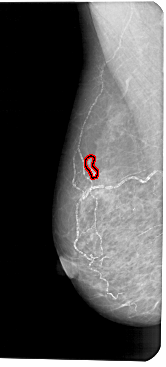

FILE: A_1191_1.LEFT_MLO.OVERLAY

TOTAL_ABNORMALITIES 1

ABNORMALITY 1

LESION_TYPE CALCIFICATION TYPE PLEOMORPHIC DISTRIBUTION LINEAR

ASSESSMENT 4

SUBTLETY 2

PATHOLOGY MALIGNANT

TOTAL_OUTLINES 1

BOUNDARY